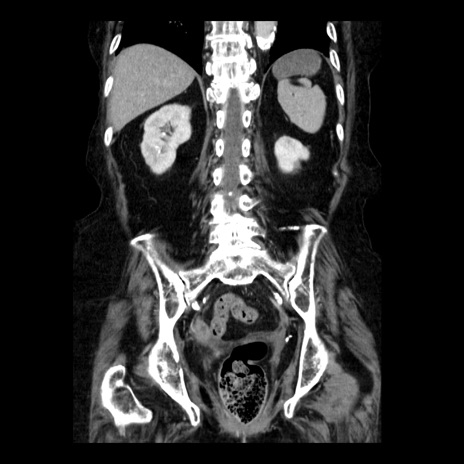

症例14(冠状断像)

【症例】 90歳代女性

【主訴】 腹痛・嘔吐

【現病歴】今朝から左側腹部痛を認めた。 経過観察していたが、嘔吐を認めたため来院。

【既往歴】 子宮癌術後

【身体所見】 意識清明、BP 127/54mmHg、P 98bpm Sp02 95%(RA)、BT 35.8°C、腹部平坦・軟腸ぜん動音聴取良好、右下腹部圧痛(+) 反跳痛なし

【データ】WBC 9800、CRP 0.46